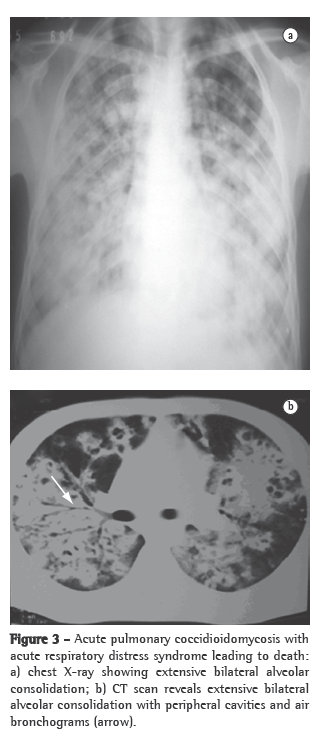

Nonspecific tests that are useful for the evaluation of patients include X-rays and CT scans of the affected site, principally of the chest, and can greatly aid in the diagnosis (Figures 2 and 3). The most common findings on chest X-rays are multiple lung nodules of peripheral distribution, associated with parenchymal consolidation. CT scans of the chest reveal peripheral lung nodules that are predominantly cavitated.(29,39)